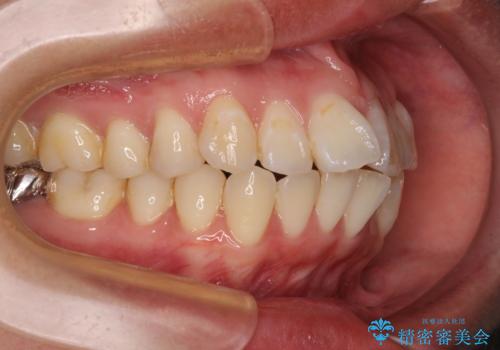

- 上下の出っ歯を気にして来院された患者様です。

口元を積極的に引っ込めるために、上下左右の第一小臼歯を4本抜歯することとしました。

また、上下前歯は舌の突出癖による開咬となっていたため、舌のトレーニングを徹底するよう指示しました。

舌突出癖の改善トレーニングは、仕上がり、治療期間、そして治療後の後戻りに大きな影響を及ぼします。

トレーニングをしっかりと行っていただいたため、スッキリとした口元に仕上がりました。